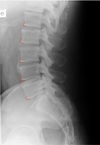

LATERAL LUMBOPELVIC LANDMARKS lateral lumbopelvic view

intervertebral disc space

123

Lateral lumbopelvic view

transverse processes l1-l5

124

vertebral body l1-l5

125

intervertebral foramen l1-l5

126

inferior endplate tips

127

Superior end plate tips